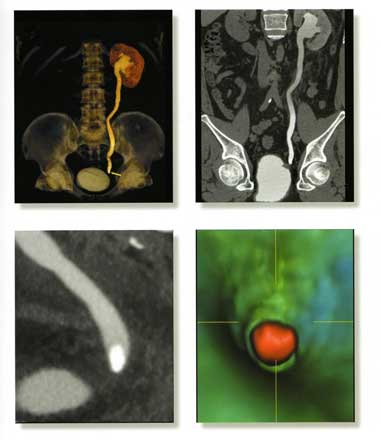

опухоли почек, мочевого пузыря на самых ранних стадиях; мочекаменная болезнь.

Все вышеизложенные методы диагностики проводятся с помощью Мультисрезового спирального компьютерного томографа Toshiba (Asteion Super 4) - 26 декабря 2006 года выпуска, который находится на базе 19-й городской больницы.

Аппарат Toshiba Astieon Super 4: относится к системе 3 поколения с непрерывным оборотом трубки и наиболее подходит для исследования головного мозга и всего тела включая исследования сердечно – сосудистой системы. Многосрезовая технология системы Asteion позволяет получать действительно изотропные объёмные данные. Эта технология позволяет расширить применение КТ и значительно увеличивает диапазон исследований.